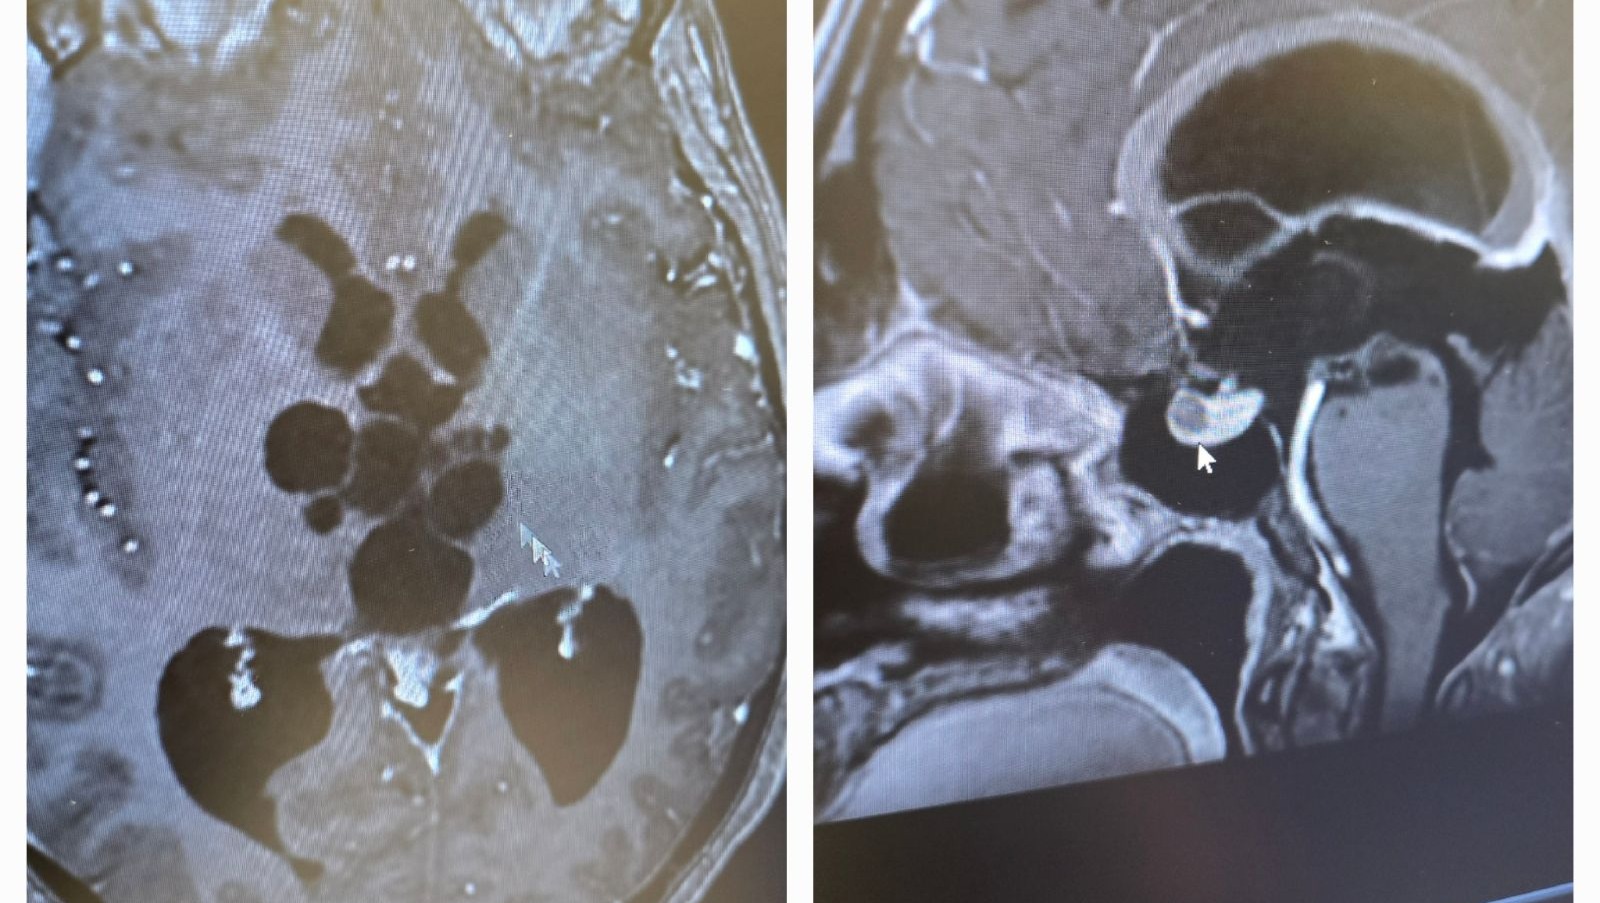

The ER doctor explained that they found some 'weird stuff' on my CT scan, and so they sent me for an MRI. To my complete surprise, the MRI showed a large mass of benign cysts in my pineal gland. These cysts (called atypical arachnoid cysts) could have been there from birth or have developed randomly at any point throughout my life, we simply don't know. What we do know is that the cysts are blocking the drainage of cerebrospinal fluid in my brain, causing a condition known as hydrocephalus, or 'water on the brain.'

The black voids in the center of my brain in these images show the build-up of excess fluid.